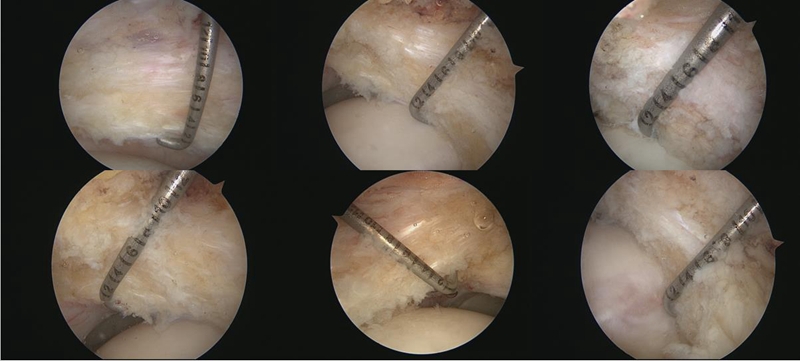

同时,也通过关节镜下进行了评估和测量。采用关节囊纵切的方式,就有机会测量到关节囊中段的厚度。通过镜下测量发现,BDDH组和FAI组的中位值分别是6mm和7mm。